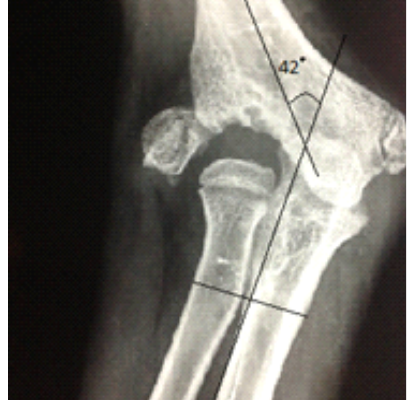

Clinical and Radiological Outcome following Kim’s Step cut Translation Osteotomy for Cubitus Varus and Valgus in Children

Volume 2 | Issue 2 | May-Aug 2016 | Page 34-37|Dhurvas Ramlal…